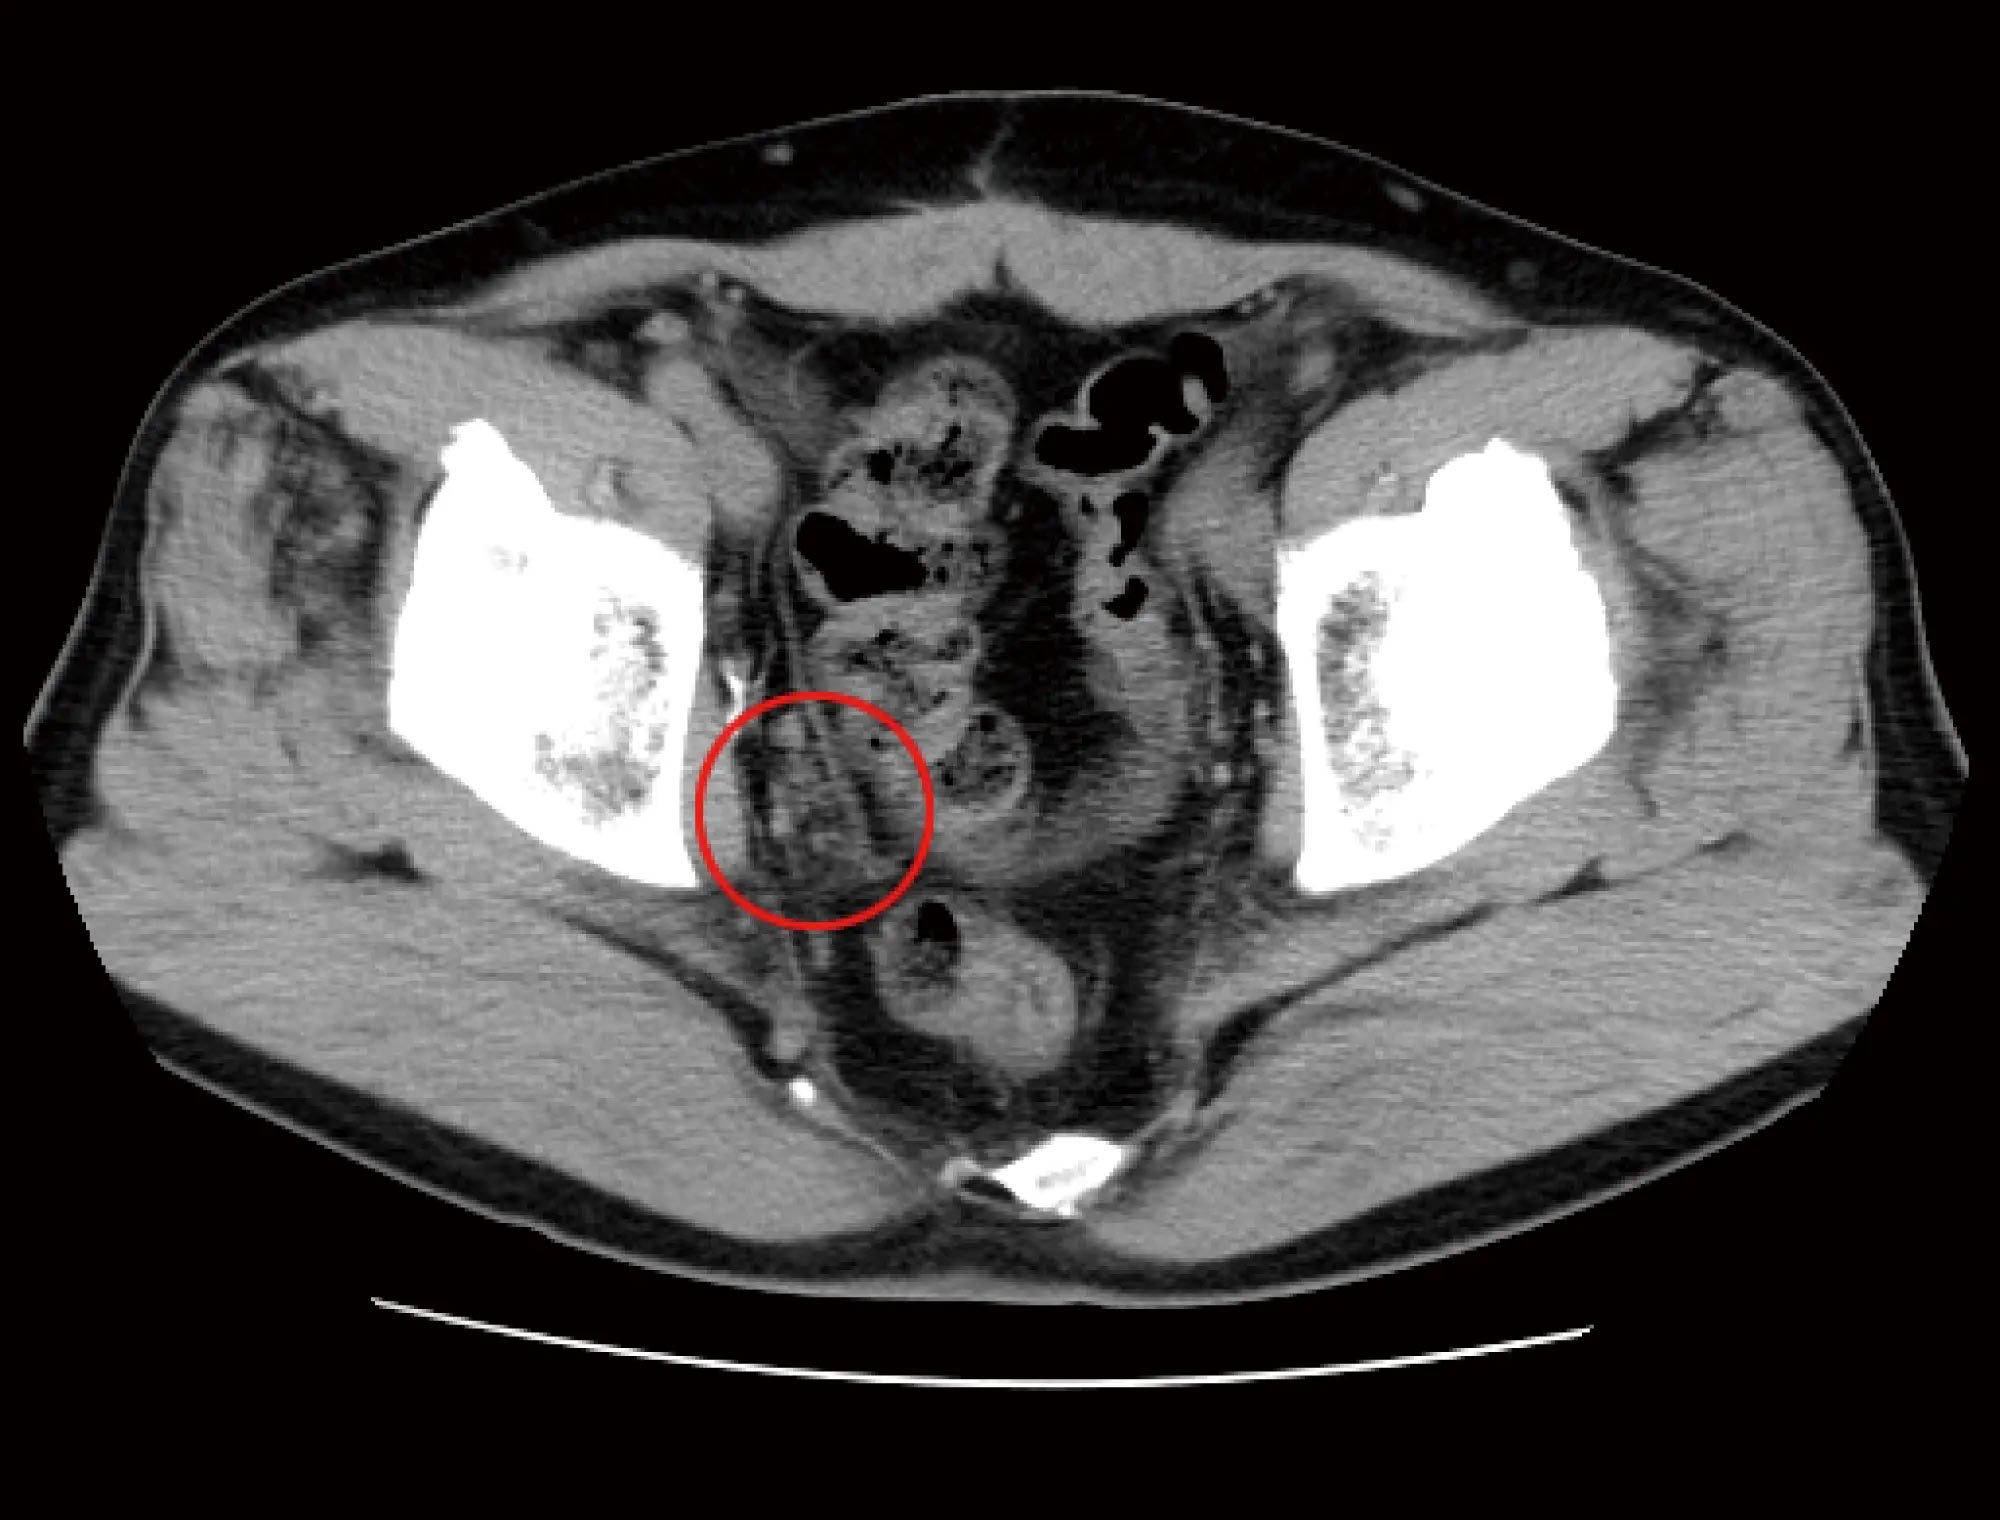

HOT ! 前立腺癌 前立腺がんの再発・転移を高精度で検出する最先端画像診断~阪大

前立腺癌 前立腺がんの再発・転移を高精度で検出する最先端画像診断~阪大の詳細情報

前立腺がんの再発・転移を高精度で検出する最先端画像診断~阪大。前立腺がん|よつかいどう泌尿器科クリニック|排尿障害・尿路。第109回日本泌尿器科学会レポート】オリゴ転移前立腺がんに。前立腺がんの合併症を予防し、治療成績向上にも寄与。「前立腺癌」都築 豊徳 / 渡邉 昌俊定価: ¥ 15000#都築豊徳 #都築_豊徳 #渡邉昌俊 #渡邉_昌俊 #本 #自然/医療・薬学・健康。「ハイドロ

• 前立腺がんの再発・転移を高精度で検出する最先端画像診断~阪大

• 前立腺がん|よつかいどう泌尿器科クリニック|排尿障害・尿路

• 第109回日本泌尿器科学会レポート】オリゴ転移前立腺がんに

• 前立腺がんの合併症を予防し、治療成績向上にも寄与。「ハイドロ